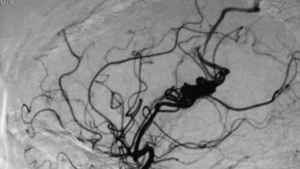

两位分别是16岁的少年和56岁的男士,在没有任何征状时做了详尽的脑及脑血管结构检查,3D三维立体磁力共振脑血管造影显示两人的大脑都有先天性的脑血管动静脉畸形血管瘤,在血管外科医生建议下,经过一段时间的观察和保守治疗,其后利用了微创脑血管导管堵塞手术、加上放射治疗,畸形血管瘤得到了有效根治,病人与生俱来的大脑计时炸弹得以拆除,消除了他们将来出血性中风的风险。

3D 三维立体脑血管造影显示,左边大脑有先天性的脑血管动静脉畸形 (AVM)。